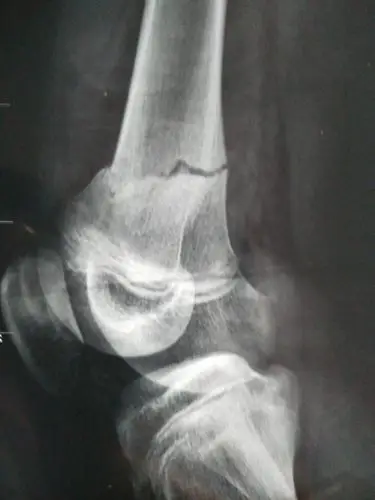

右股骨远端开放粉碎性骨折

股骨远端骨折(右侧髁上髁间)

股骨远端开放性粉碎性骨折